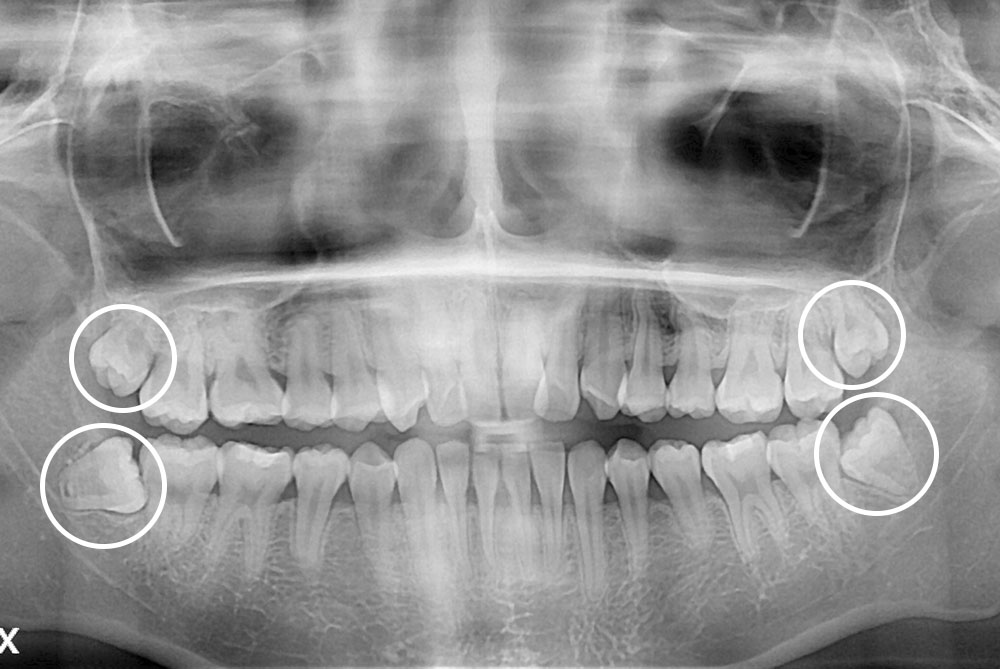

[사랑니] 매복 사랑니 발치

치료전 : 2019-02-27